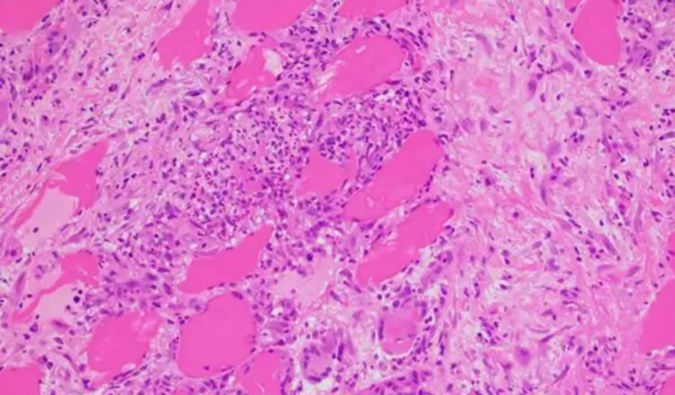

ÃÀ¸ß÷ÌṩÖÜÈ«µÄ¶¾ÀíѧÑо¿Ð§ÀÍ£¬£¬£¬£¬ÓÃÓÚÆÀ¹ÀÒ©ÎﻯºÏÎïµÄÇå¾²ÐÔÌØÕ÷¼°Ç±ÔÚΣº¦¡£¡£¡£¡£¡£¡£ÃÀ¸ß÷רҵÍŶÓϸÃÜÅäºÏ¿Í»§£¬£¬£¬£¬Æ¾Ö¤î¿ÏµÒªÇóºÍÏîÄ¿µÄÏêϸÐèÇ󣬣¬£¬£¬Á¿Éí¶¨ÖÆÑо¿¼Æ»®¡£¡£¡£¡£¡£¡£

ÒÀÍÐÏȽøµÄÑз¢Æ½Ì¨¡¢ÍêÉÆµÄʵÑéÉèÊ©¡¢ÂÄÀú¸»ºñµÄ¿ÆÑ§¼ÒÍŶÓÒÔ¼°¶ÔÖ¤Á¿µÄÑÏ¿á°Ñ¿Ø£¬£¬£¬£¬ÃÀ¸ß÷Äܹ»Îª¿Í»§Ìṩ¸ßÖÊÁ¿¡¢¿É¿¿ÇÒÇкÏGLP¹æ·¶µÄ¶¾ÀíѧÊý¾Ý£¬£¬£¬£¬ÒÔÖ§³ÖÇå¾²ÓÐÓÃÒ©ÎïµÄÑз¢¡£¡£¡£¡£¡£¡£×èÖ¹2025Äê6ÔÂ⣬£¬£¬£¬ÃÀ¸ß÷ÒÑΪȫÇòÁè¼Ý2000¼Ò¿Í»§ÌṩЧÀÍ£¬£¬£¬£¬ÀÖ³ÉÖúÁ¦580Óà¸öINDÉêÇë»ñÅú£¬£¬£¬£¬³ä·ÖÕ¹ÏÖÁËÎÒÃÇÔÚÌṩ¸ßÖÊÁ¿Ð§ÀͺÍÍÆ¶¯È«ÇòÒ©ÎïÑз¢Àú³Ì·½ÃæµÄÄÜÁ¦

·ÇGLPÓëGLP¶¾ÀíѧÑо¿

• µ¥´Î¸øÒ©¶¾ÐÔÊÔÑ飨Äö³ÝÀàºÍ·ÇÄö³ÝÀà£©ÖØ¸´¸øÒ©¶¾ÐÔÊÔÑ飨Äö³ÝÀàºÍ·ÇÄö³ÝÀࣩÒÅ´«¶¾ÐÔÊÔÑéÃâÒßÔ­ÐÔÊÔÑé¶¾´ú¶¯Á¦Ñ§¾Ö²¿¶¾ÐÔÊÔÑ飨ÈÜѪ¡¢¹ýÃô¡¢´Ì¼¤ÐÔÊÔÑ飩Ö°©ÐÔÑо¿Ð¸øÒ©¼¼ÊõµÄ¶¾ÀíÊÔÑ飺ÎüÈë¶¾ÀíADC Çå¾²ÐÔÆÀ¼ÛÇå¾²Ò©ÀíÊÔÑ飺ÖÐÊàÉñ¾­ÏµÍ³Ñо¿¡¢ÐÄѪ¹Üϵͳ£¨È®ºÍºïµÄÒ£²âºÍ·ÇÒ£²â¼¼Êõ£©¡¢ºôÎüϵͳ¡¢hERGÉúÖ³¶¾ÐÔÊÔÑé[ÉúÓýÁ¦ÓëÔçÆÚÅßÌ¥·¢Óý¶¾ÐÔÊÔÑé(ÉúÖ³I¶Î)¡¢ÅßÌ¥-Ì¥×з¢Óý¶¾ÐÔÊÔÑ飨ÉúÖ³II¶Î£©¡¢Î§²úÆÚ¶¾ÐÔÊÔÑ飨III ¶Î£©£¬£¬£¬£¬»ò¸÷¶Î×éºÏʽÊÔÑé¡£¡£¡£¡£¡£¡£]